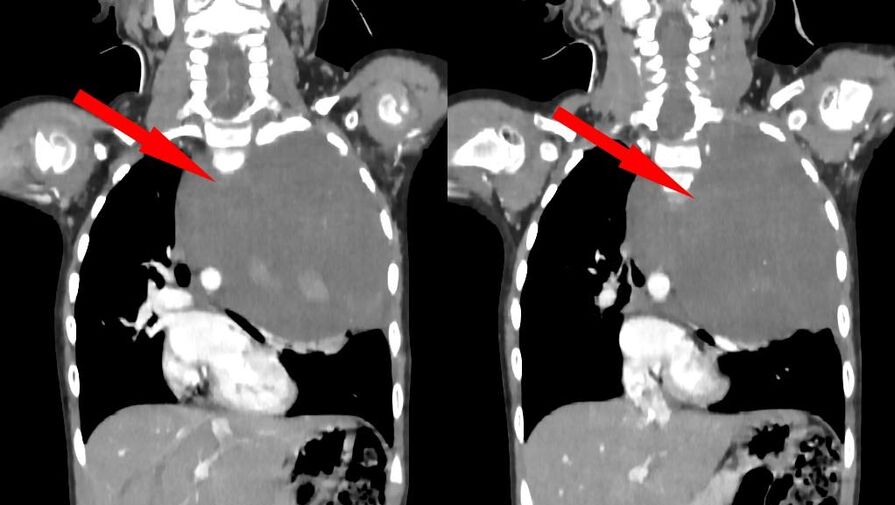

Родители показали дочь врачам, когда заметили у нее небольшую припухлость в области шеи. Специалисты по месту жительства выявили огромное новообразование размером со страусиное яйцо, которое сдавливало сердце и легкое. Сквозь ткань опухоли проходили крупные сосуды: «позвоночная артерия, питающая головной мозг, и подключичная артерия с ее ветвями, питающая левую руку». После телемедицинской консультации ребенка направили в Москву.

«Учитывая гигантский размер опухоли и ее расположение вблизи множества жизненно важных структур, мы использовали расширенный доступ по типу «раковины моллюска». Он предполагает рассечение не только межреберного промежутка, но и самой грудины, что позволяет «раскрыть» грудную клетку, как раковину», — рассказал заведующий отделением реконструктивной и восстановительной хирургии грудной полости РДКБ, к.м.н. Евгений Андреев об операции.